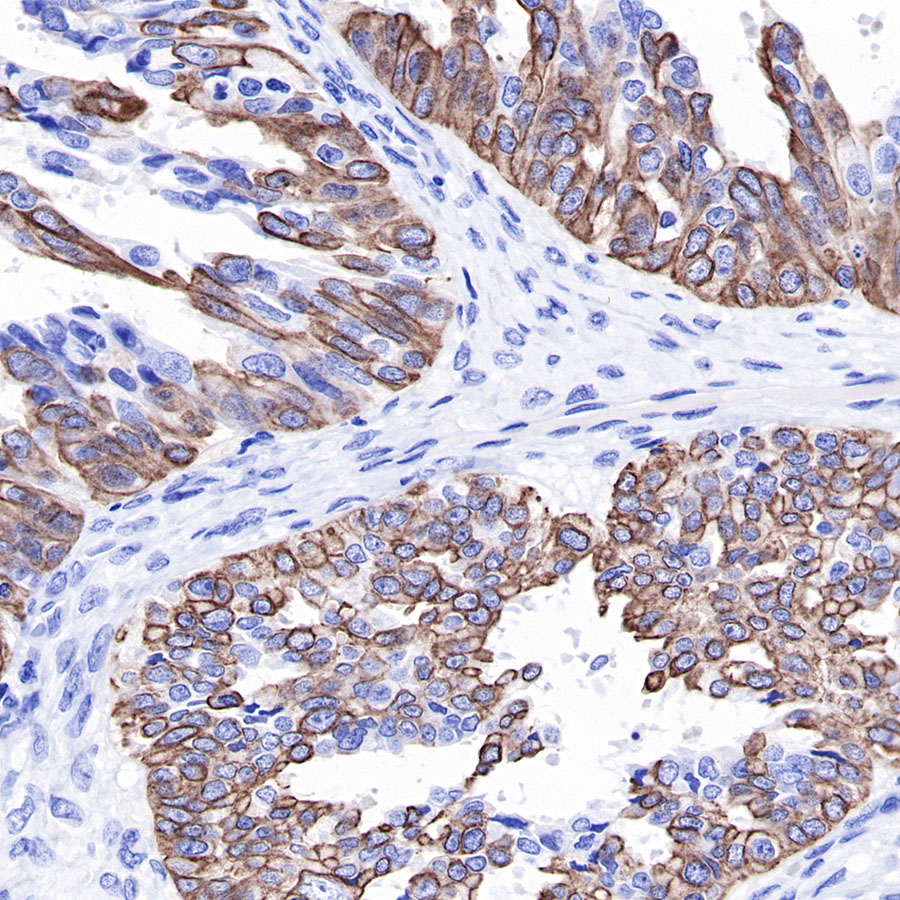

| IHC-P |

1:2000 |

Background

Cytokeratins are proteins of cytoskeletal intermediate filaments, and their main function is to enable cells to withstand mechanical stress. In humans, 20 different cytokeratin isotypes have been identified. Cytokeratins 8, 18, 19, and 20 have been associated with bladder. Cytokeratin 18 (KRT18, also called K18), found in epithelial cells, is released from hepatocytes upon death.